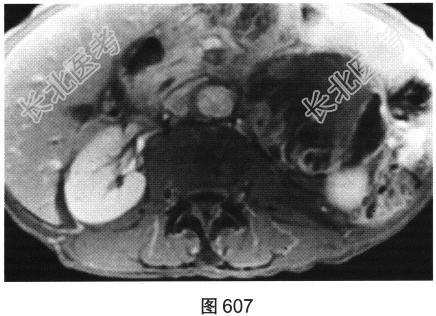

- 多项选择题3.患者进一步行MRI检查,对MRI影像特征描述正确的是( )

A、可见淋巴结转移

B、T2WI以低信号为主

C、增强无强化

D、病灶信号不均匀

E、增强可见分隔状强化

F、T2WI以高信号为主

关注下方微信公众号,搜题查看答案

- 多项选择题4.患者最可能的诊断为( )

A、结核

B、淋巴瘤

C、转移瘤

D、腹膜后肉瘤

E、主动脉瘤

F、血管平滑肌脂肪瘤